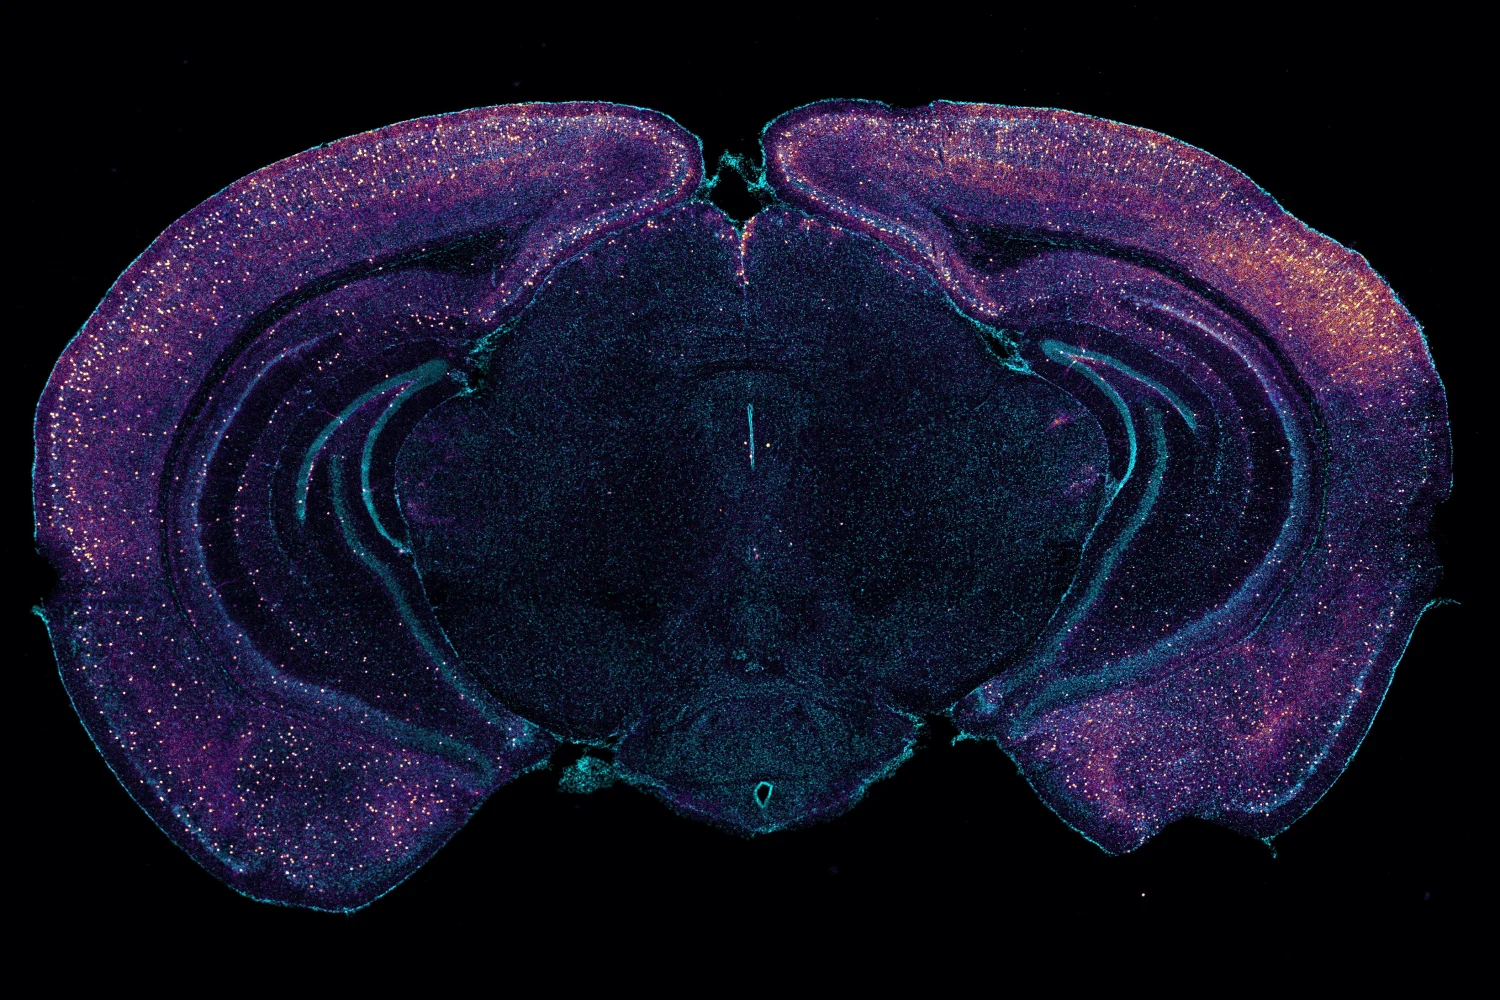

Researchers have discovered that changing the body's natural sleep-wake rhythm, specifically by targeting a protein called REV-ERBα, protects the brain in mouse models of Alzheimer's disease (ScienceDaily). This intervention boosts NAD+, a molecule crucial for brain cell energy and repair, while reducing toxic tau protein accumulation—the latter being a hallmark of Alzheimer’s pathology (Popular Mechanics).

The circadian protein REV-ERBα regulates daily rhythms of metabolism and inflammation, and its inhibition in the brain has shown neuroprotective effects in mice (Washington University in St. Louis).